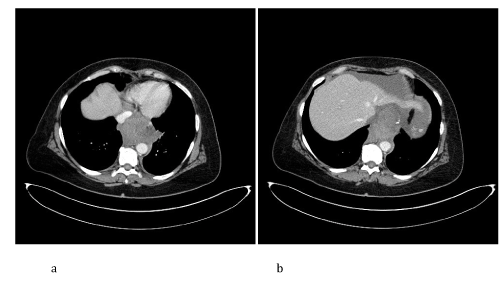

CT Imaging findings suggested the presence of splenic artery aneurysmatic dilatation, which can’t be separeted from the gastric wall, close to surgical clips of the previous Sleeve gastrectomy (Figure 1). A mediastinal hematoma constricted the esophagus (Figure 2). Fat stranding of the retroperitoneal space, hemoperitoneum (Figure 3) and ischemic injuries of the spleen were present (Figure 4).

Figure 2. CT axial images after intravenous injection of iodinated contrast agent demonstrate a, b) the presence of mediastinal cloth, with distal intrathoracic esophagus compression